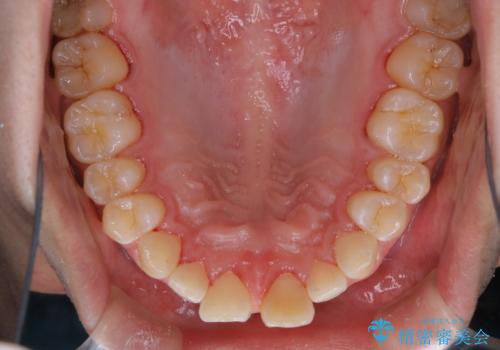

矯正治療中は虫歯や歯周病リスクが高くなることがあります。

インビザライン矯正治療はマウスピースで1日20時間以上歯列全体を覆っているため、歯石や汚れなどが付着したままだと、フィットが悪くなったり、口臭が強く出たりする原因につながることもあります。

今後、矯正を考えている場合は、まず現状の口腔内をチェックし、虫歯や歯周病などを早期に発見し進行を防ぐことが大切です。